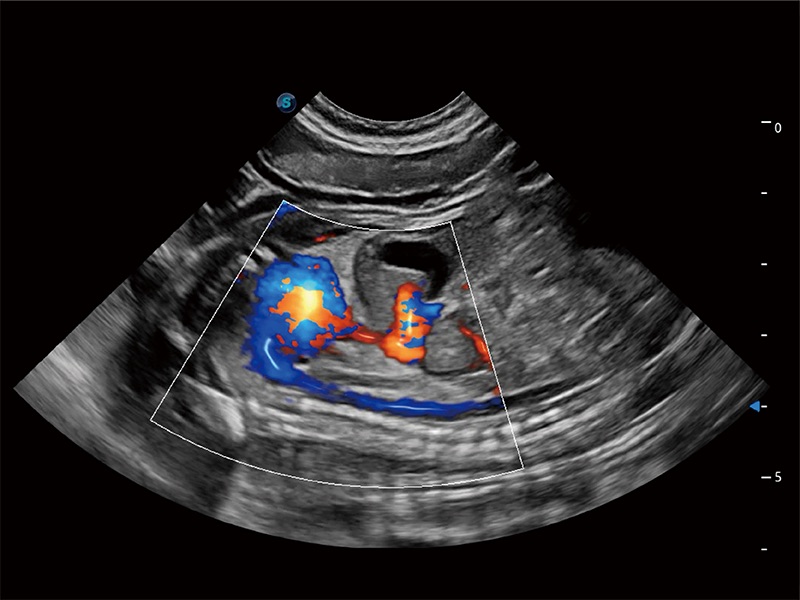

極大提升超低速微細血流的檢出能力,同時更精準地濾除軟組織和超聲信號,為獸用醫(yī)生提供以往無法通過常規(guī)血流獲得的疾病診斷信息。

高性能和先進的臨床應用工具可以為動物醫(yī)生提供臨床信心。ProPet 80 搭載了先進的腹部和淺表應用工具,幫助醫(yī)生在日常臨床實踐中發(fā)揮前所未有的作用。